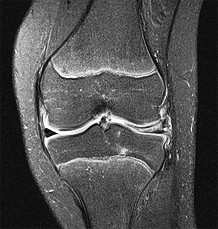

A 22-year-old female soccer player undergoes primary anterior cruciate ligament (ACL) reconstruction using a bone-patellar tendon-bone autograft. Postoperatively, she experiences loss of terminal extension and anterior knee pain. An MRI indicates graft impingement against the intercondylar roof. Which of the following technical errors during tunnel preparation is the most common cause of this specific impingement pattern?

Options:

Correct Answer: Tibial tunnel placed too anteriorly

Explanation:

Placing the tibial tunnel too anteriorly is the most common cause of intercondylar roof impingement. The tibial tunnel should be placed posterior to the intersection of Blumensaat's line and the tibial plateau when the knee is in full extension. If placed anterior to this line, the graft will impinge on the notch roof during terminal extension, leading to a loss of extension and potential graft failure.